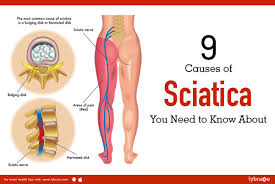

Download Sciatic nerve pain pictures